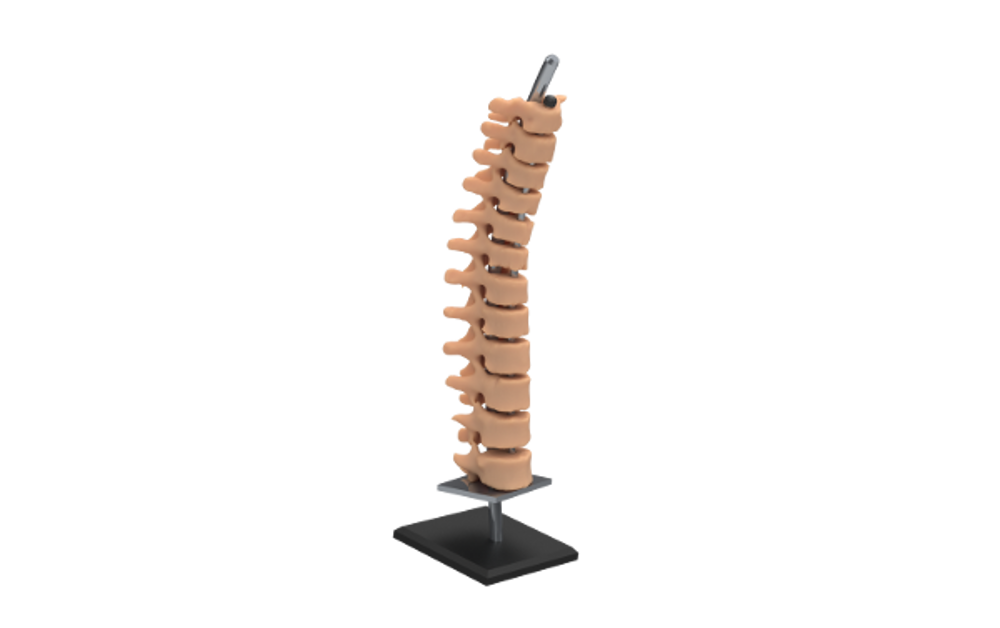

TRINOTA aims to help doctors assess patient specific treatment efficacy with the use of 3D visualization (Physical and Digital Models) of a patient's region of interest (ROI).

With the use of our Ultra High Resolution Professional Grade 3D Printer, we can produce physical models of the patient's ROI.